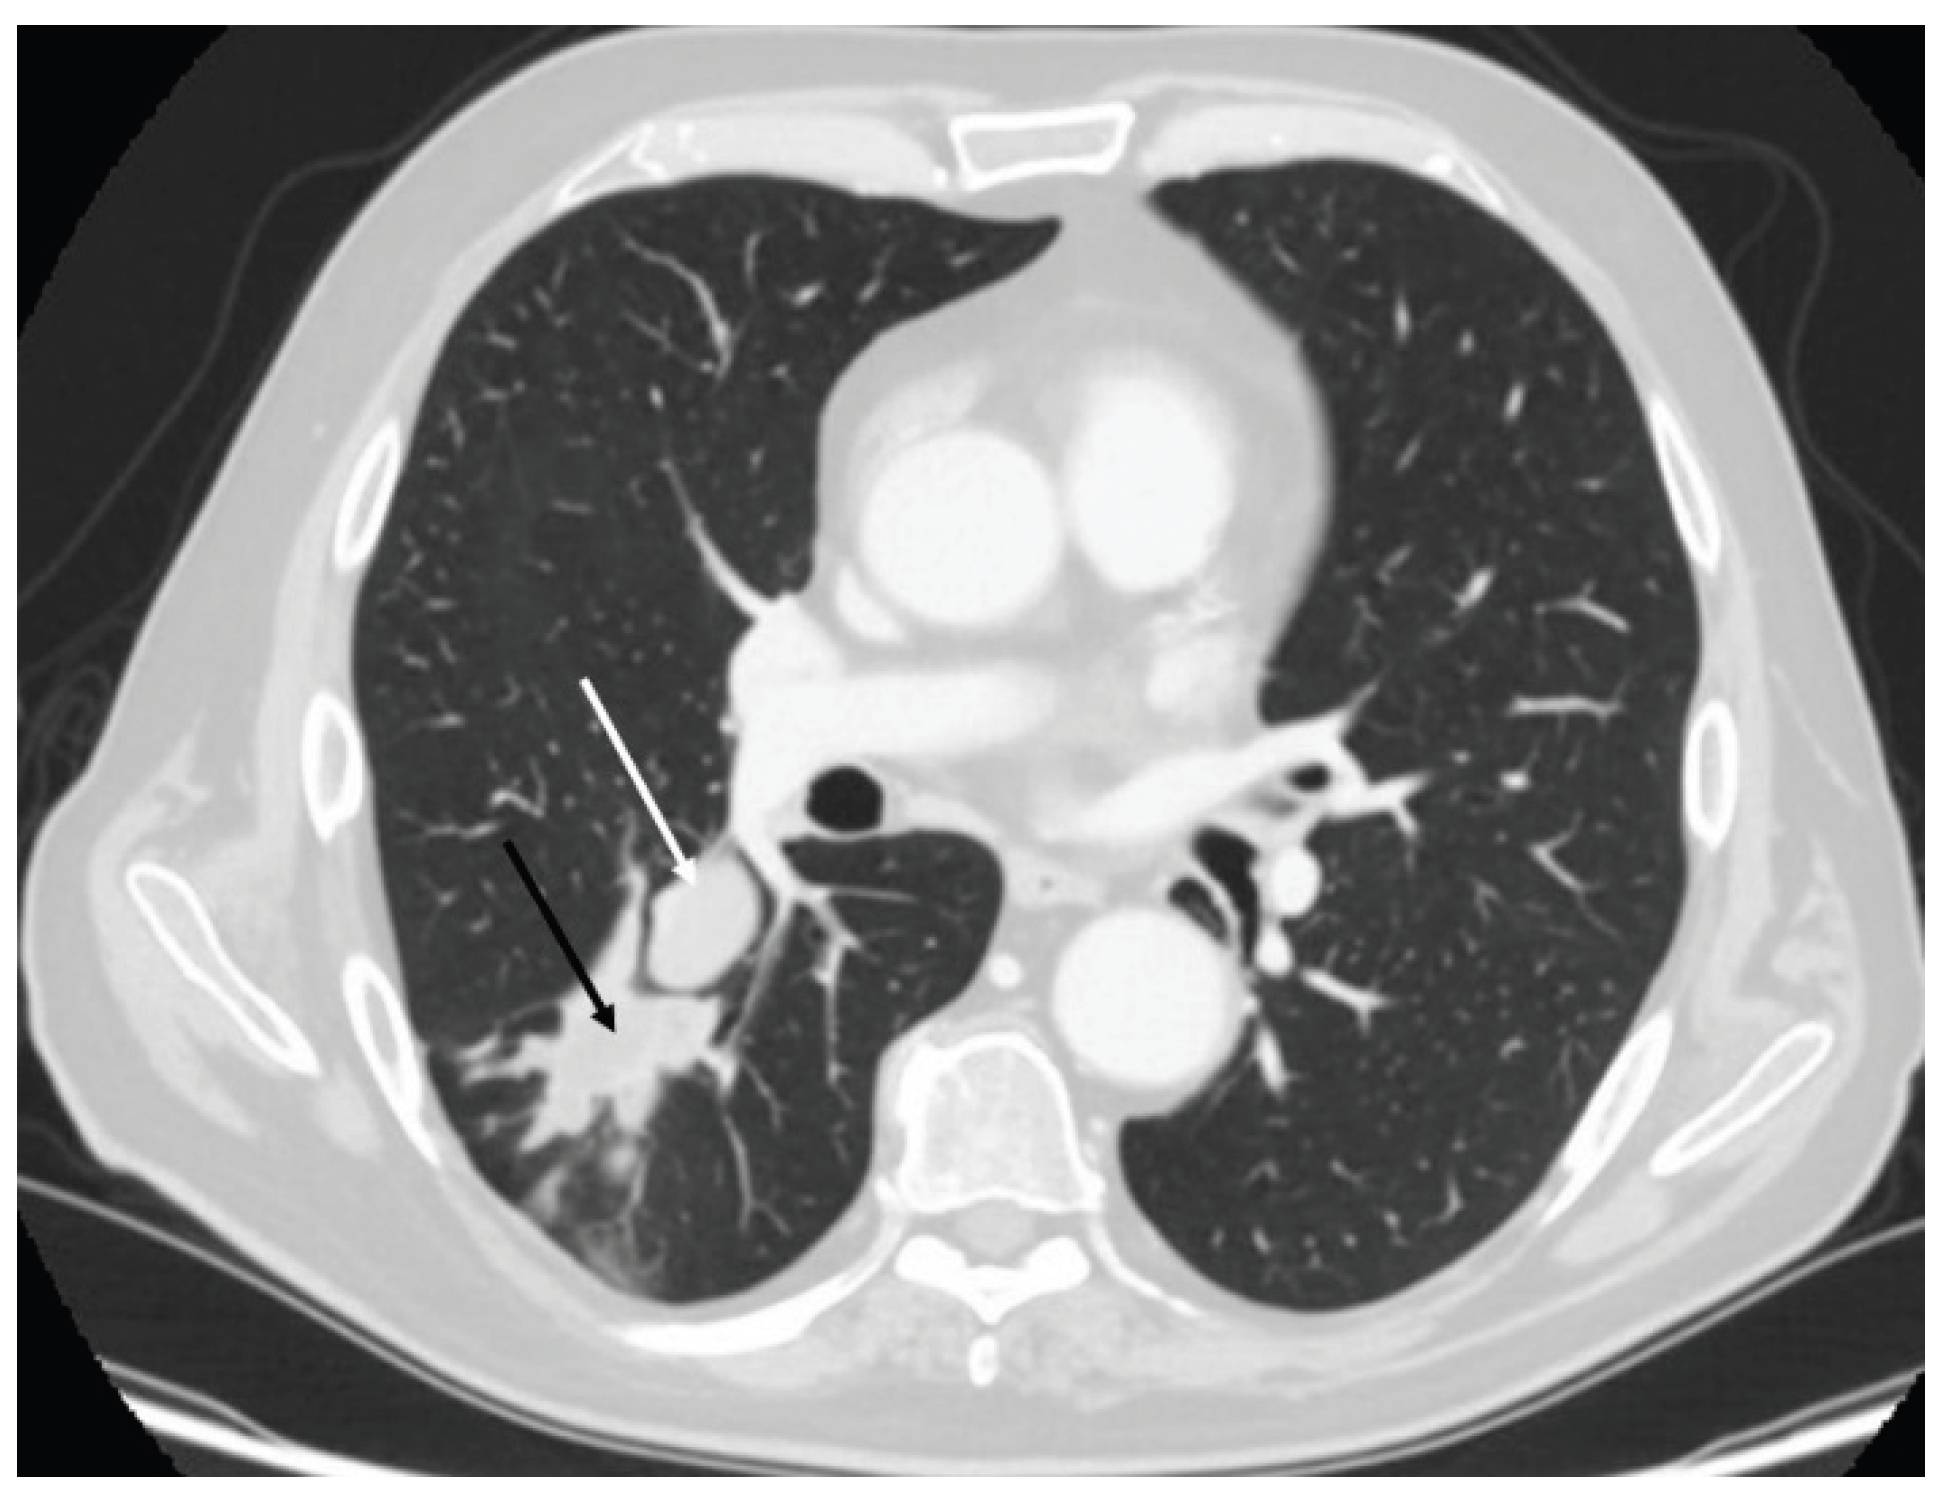

3.2. Radiology

- Meisinger QC, Klein JS, Butnor KJ, Gentchos G, Leavitt BJ. CT features of peripheral pulmonary carcinoid tumors. AJR Am J Roentgenol. 2011 Nov;197(5):1073-80. [CrossRef]

- Baettig E, Molina-Centelles MF, Amr-Rey A, Mancheño-Franch N, Muñoz-Núñez C. Pulmonary neuroendocrine cells: Spectrum of diseases and their radiological-pathological correlations. Radiologia (Engl Ed). 2025 May-Jun;67(3):357-364. [CrossRef]